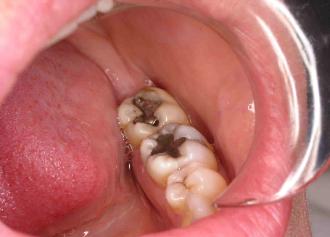

The patient below has 2 defective, decayed amalgam fillings.  We removed the decayed amalgams

and placed white bonded composite fillings.